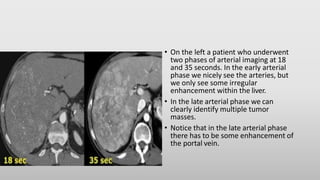

• The CT-images show an early arterial phase in comparison to a late arterial

phase.

• The CT-images are of a patient who underwent two phases of arterial

imaging at 18 and 35 seconds.

In the early arterial phase we nicely see the arteries, but we only see some

irregular enhancement within the liver.

In the late arterial phase we can clearly identify multiple tumor masses.

• On the left a patient who underwent

two phases of arterial imaging at 18

and 35 seconds. In the early arterial

phase we nicely see the arteries, but

we only see some irregular

enhancement within the liver.

• In the late arterial phase we can

clearly identify multiple tumor

masses.

• Notice that in the late arterial phase

there has to be some enhancement of

the portal vein.

• On theleft a patient who underwent two phases of arterial imaging at 18 and 35 seconds. In the early arterial phase we nicely see the arteries, but we only see some irregular enhancement within the liver. • In the late arterial phase we can clearly identify multiple tumor masses. • Notice that in the late arterial phase there has to be some enhancement of the portal vein.